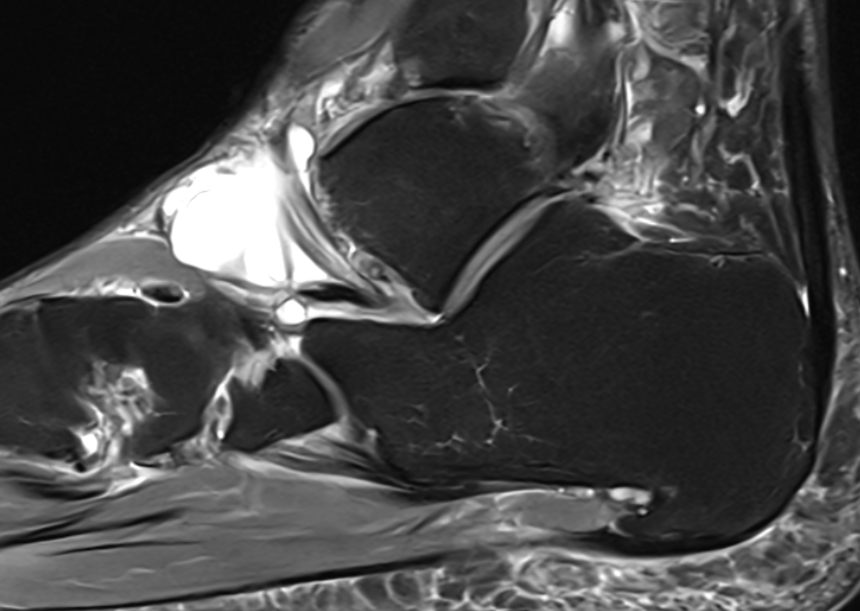

GCT flexor tendon sheath

GCT of tibialis posterior tendon sheath